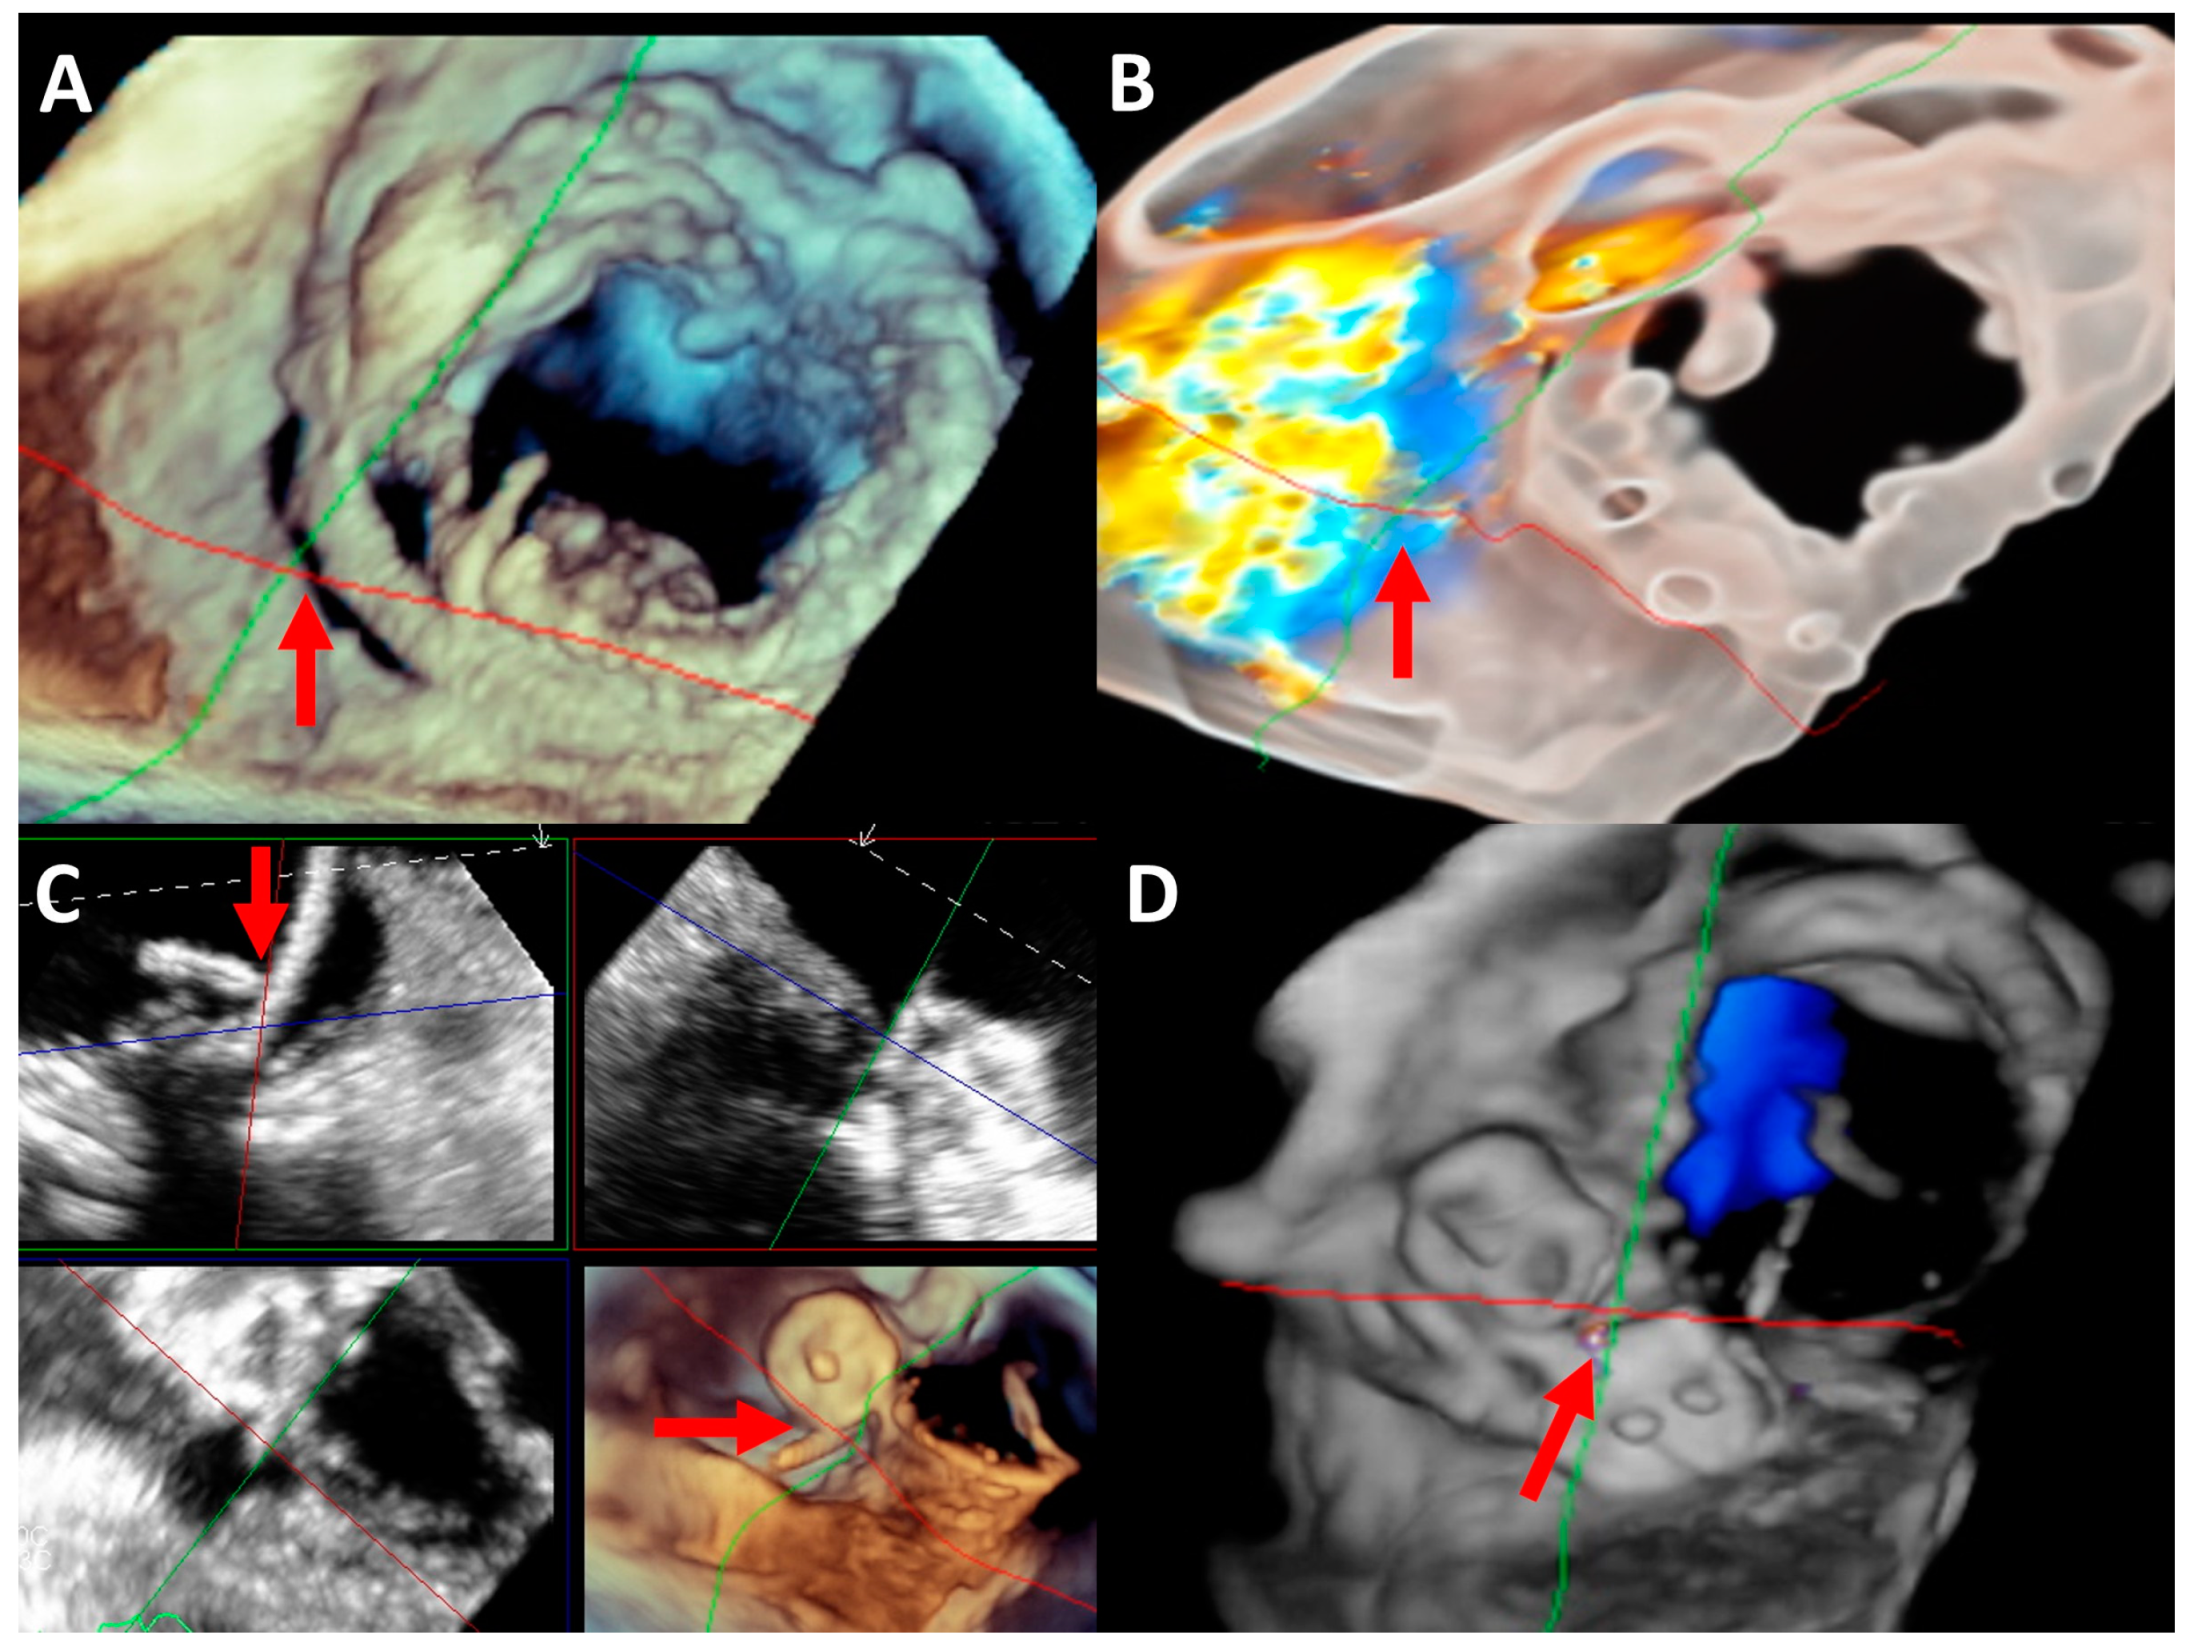

2.5. Imaging Evaluation

2.6. Procedure

5. Mitral Paravalvular Leak Closure